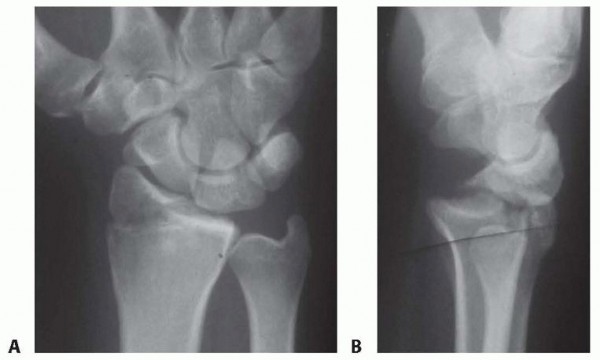

Arthroscopic Reduction and Fixation of Distal Radius and Ulnar Styloid Fractures